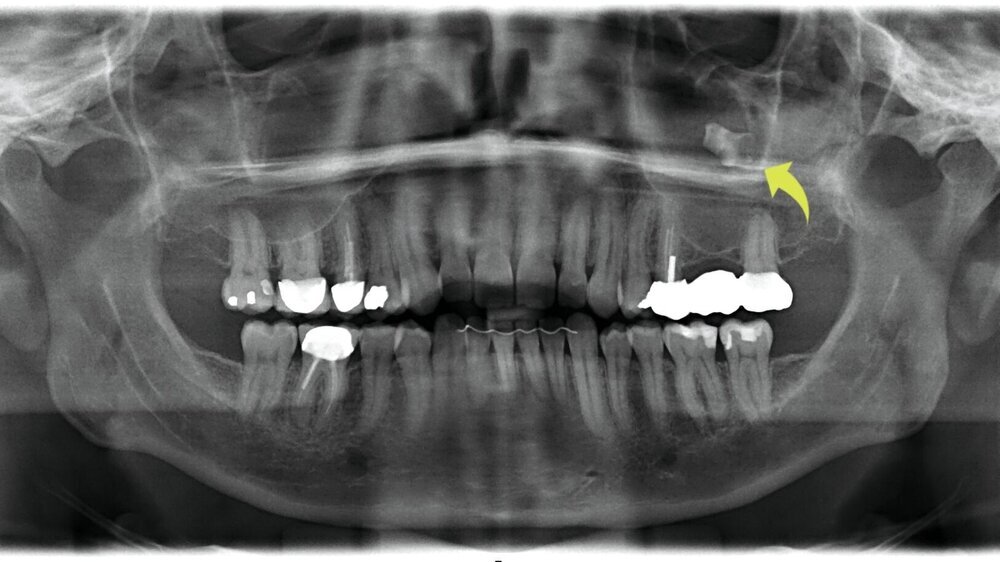

Ein 49-jähriger Patient stellte sich in unserer mund-, kiefer- und gesichtschirurgischen Praxis im Rahmen einer schlafmedizinischen Beratung vor. Im Rahmen der standardisierten radiologischen Eingangsuntersuchung mittels Panoramaschichtaufnahme zeigte sich als Zufallsbefund eine röntgendichte Verschattung des linken Sinus maxillaris regio 26. Der Molar war bereits vor längerer Zeit extrahiert worden, der genaue Zeitpunkt ließ sich nicht mehr eruieren. Die entstandene Schaltlücke war bei der Vorstellung durch eine festsitzende Brückenkonstruktion geschlossen (Abbildung 1). Klinische Beschwerden bestanden nicht.

Zur weiteren Abklärung erfolgte eine digitale Volumentomografie (DVT), die eine subtotale Verschattung der linken Kieferhöhle sowie einen stark röntgendichten, metallisch anmutenden Fremdkörper von etwa 7 mm Größe zeigte. Weiter imponierte ein deutlicher vertikaler und horizontaler Knochenverlust im Bereich der ehemaligen Extraktionsalveole (Abbildung 2). Eine klinisch manifeste Mund-Antrum-Verbindung konnte jedoch nicht festgestellt werden.